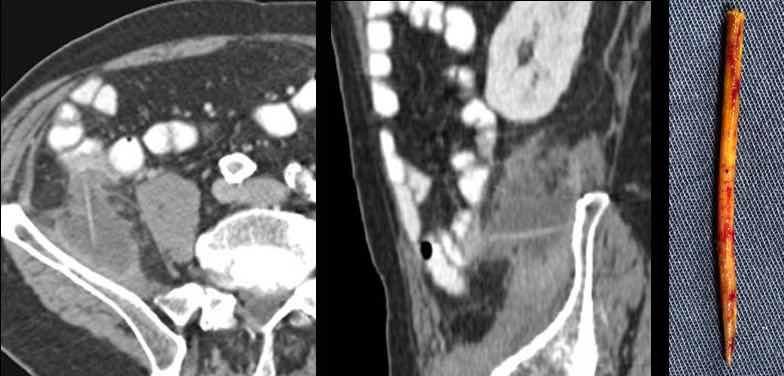

Bệnh nhân nam 75 tuổi với nghi ngờ lâm sàng áp xe cơ thắt lưng chậu.

CT xác nhận áp xe và xác định một dị vật sắc nhọn thẳng, hơi tăng tỷ trọng, có vẻ đã di chuyển từ ruột non vào cơ chậu.

Hình dạng và tỷ trọng gợi ý đây là que gỗ hơn là xương cá.

Bằng phẫu thuật xâm lấn tối thiểu, cả mủ và que gỗ đều được lấy ra.

Bệnh nhân có hàm răng giả, tiền sử cắt ruột thừa và có thói quen “gạt” thịt khỏi que xiên bằng nĩa.